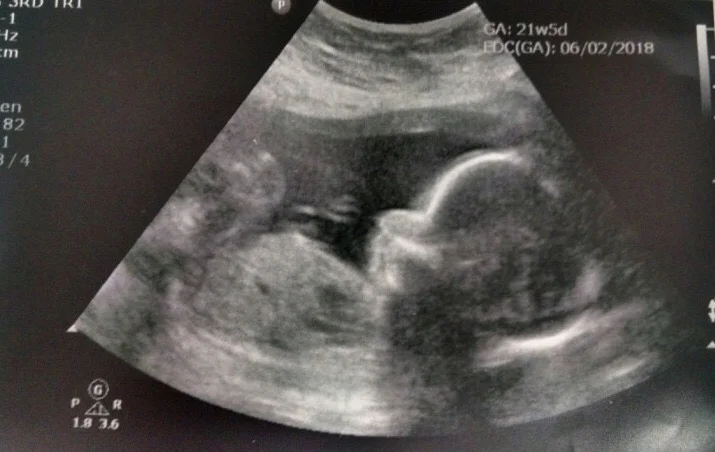

21 weeks into her pregnancy, Malinda suffered a massive stroke. After placing her on life support, the doctors declared she was beyond medical hope of recovery. Devastated by this news and the sudden grief, the family requested that the hospital keep Malinda on life support in an attempt to save the baby and bring Christopher Reuben to a safe point of delivery.